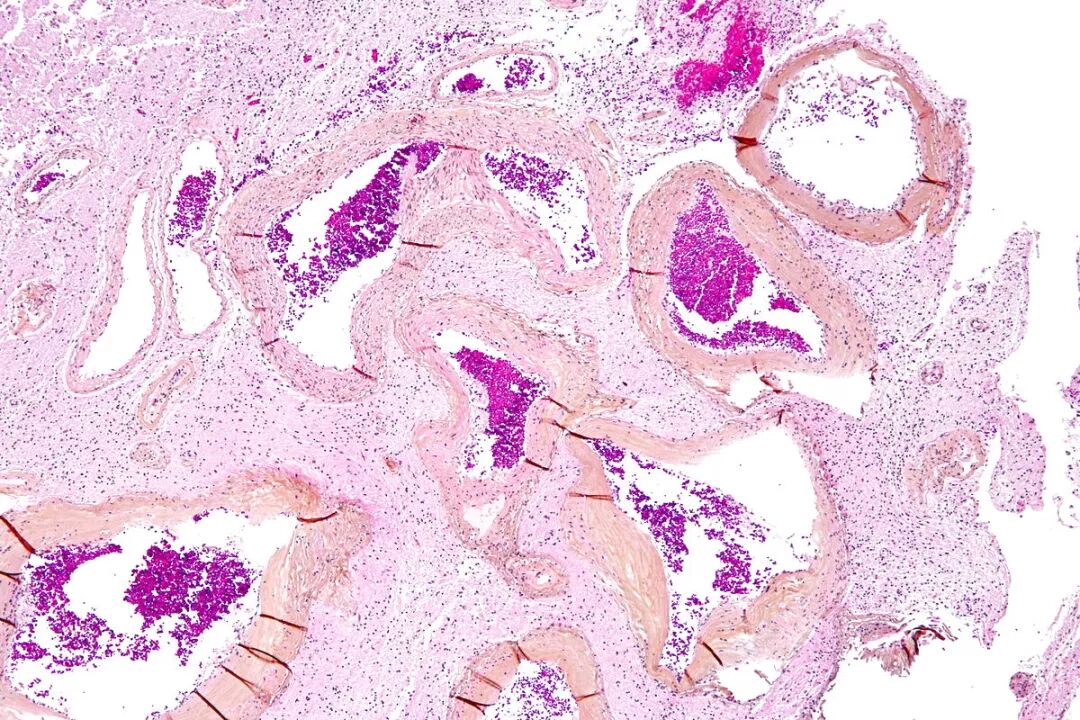

中等动静脉

中等动静脉.jpg

动静脉横切带神经 - 生物切片标本_新乡市红树林教学仪器有限公司